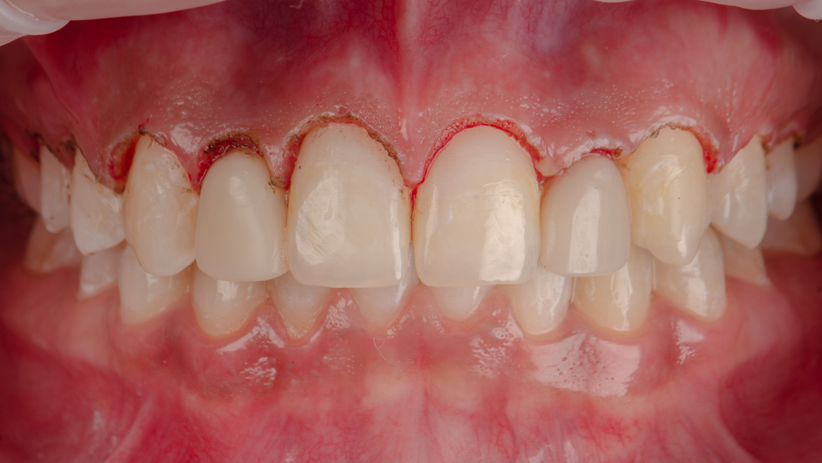

Como parte integrante do plano de tratamento, também foi realizado o aumento da coroa clínica por meio de gengivoplastia dos dentes superiores anteriores e pré-molares e o clareamento caseiro.

Após a estabilização da cor, foram realizadas todas as etapas para a confecção das coroas metalocerâmicas pelo fluxo digital. Os tecidos peri-implantares já estavam condicionados para a prótese final.

As coroas metalocerâmicas foram instaladas e as radiografias periapicais realizadas.